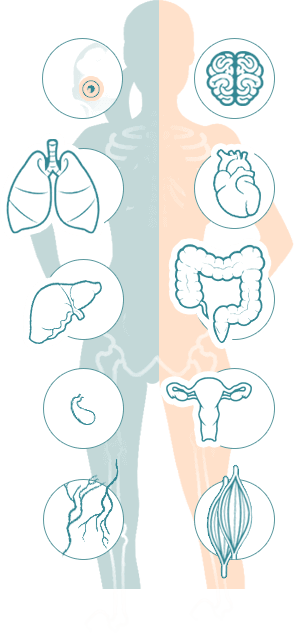

ГЕЛЬМИНТЫ ПОРАЖАЮТ ИЗНУТРИ, РАЗМНОЖАЮТСЯ И ВЫЗЫВАЮТ СМЕРТЕЛЬНЫЕ ЗАБОЛЕВАНИЯ!

ПОПУЛЯЦИЯ +200,000

Самки паразитов откладывают до 240 000 яиц в кишечнике человека ежедневно.

7-10 метров

Размеры гельминтов (глистов) колеблются от нескольких сантиметров до 7-10 метров.